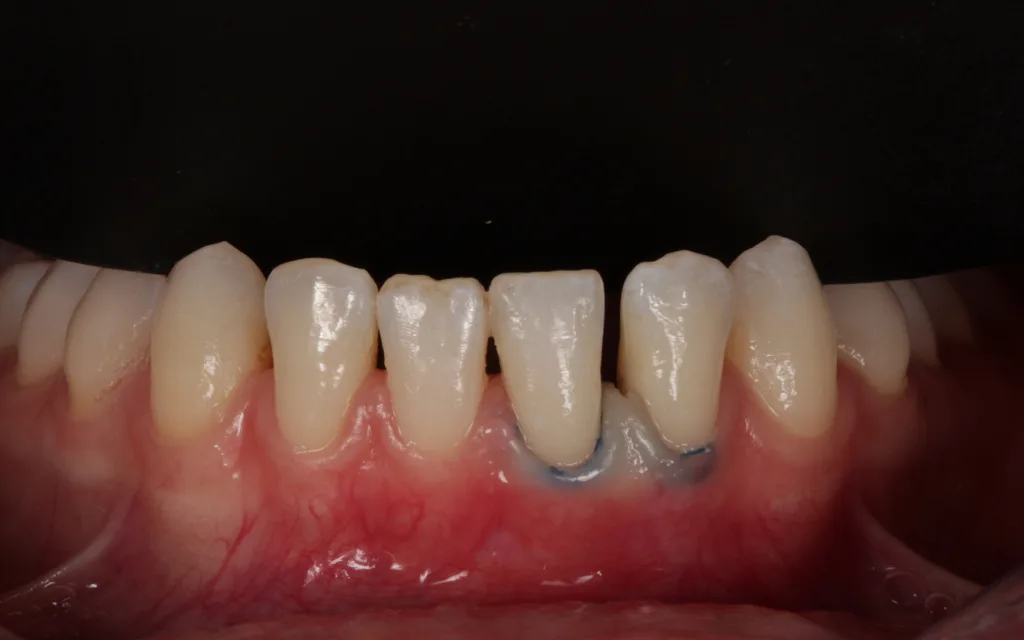

Erstbesuch und Erhebung der allgemeinmedizinischen Anamnese erfolgten am 24.10.2024. Es lagen weder Erkrankungen noch regelmäßige Medikamenteneinnahme vor. Die Patientin ließ sich aus ästhetischen Gründen 2018 alio loco die gesamte Oberkieferfront mit verblockten Zirkonkronen versorgen (Abb. 1) und kam nun für eine Zweitmeinung bezüglich ihrer unbefriedigenden Unterkiefer-Frontsituation.

EggerIhr Wunsch bestand darin, die Lücke 31/32 mit möglichst einfachen Mitteln wieder ästhetischer zu gestalten (Abb. 2). Eine kieferorthopädische und/oder prothetische Variante kam aus finanziellen Überlegungen nicht in Betracht. Nach Aufklärung und eingehender Beratung war die Patientin mit der vorgeschlagenen Behandlung einverstanden.

Im Ober- und Unterkiefer zeigt sich nur ein schmales Band an keratinisierter Schleimhaut. Die Gewebestärke entspricht einem dünnen Biotyp (Abb. 2). Die Patientin verfügt über eine mittlere bis stark geformte Ober- und Unterlippe. Die Lachlinie verläuft mittelhoch.

Weiße Ästhetik

Zahnlänge der OK-Front empfindet die Patientin als ausreichend lang. Das entspannte Lächeln zeigt ca. zwei Drittel der Frontzahnlänge. Im Unterkiefer zeigen sich ovale/dreieckige Zahnformen. Die ursprüngliche anatomische Kauflächenstruktur in den Seitenzahnbereichen ist vorhanden. Die Zahnfarbe entspricht dem Alter der Patientin.